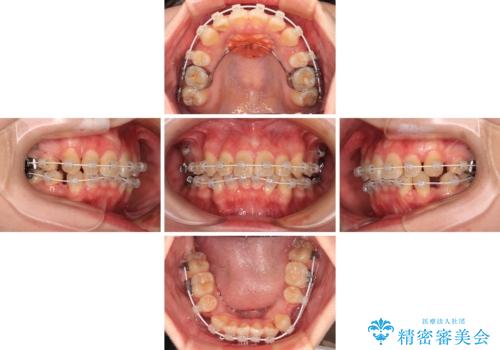

- 矯正装置

- 審美装置

口元の突出感はなかったものの、捻転や八重歯を改善するために補助装置を併用する必要がありました。

予定の2年半を越えてしまいましたが、無事にきれいな口元に仕上げることができました。